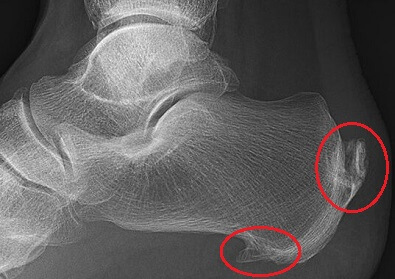

The most common cause of a hard lump on the back of the heel is a Haglund's Deformity, aka Posterior Heel Spur or Pump Bump.

Heel spurs develop when extra layers of bone form on the heel due to a build-up of calcium deposits. This is usually in response to repetitive or excessive friction or stress on the bone.

Bone spurs can also develop underneath the heel, known as inferior heel spurs. They are typically associated with plantar fasciitis and can cause a hard bump underneath the heel. Due to the surrounding soft tissues, you might not be able to feel the bump itself but it can irritate the surrounding soft tissues causing inferior heel pain.

To find out more about these hard lumps in the heel of the foot, including causes, symptoms, diagnosis and treatment, check out the Heel Bone Spurs article.

A hard lump on the heel of the foot is usually from a bone spur.

A bone spur lump on the back of the heel is called a Haglund’s Deformity, whereas a hard bump under the heel of foot is called an inferior calcaneal spur.